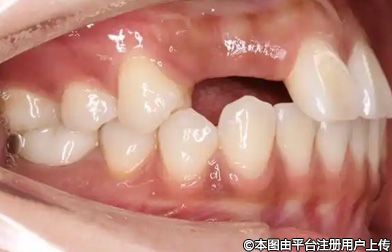

2、鄰牙、對牙、同側牙松動脫落

缺牙后不去修復,時間一久,鄰牙、對牙甚至同側牙也會跟著松動、脫落。

這是因為缺牙的地方沒有支撐,鄰牙就會在咀嚼力的作用下,慢慢移位歪斜,逐漸松動;而對頜的牙齒,沒有牙齒支撐,會越變越長,終也會松動、脫落。